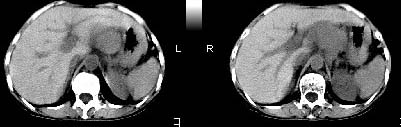

肝胃之间、胰头后、腹主a周围,融合而成团块状影,包绕血管,胰腺前移后缘分界欠清,与肝胃分界清,肿块未见明显强化,考虑淋巴瘤可能性大

胰腺受压前移,胰管扩张,应为腹膜后占位,病灶密度不均,有低密度坏死区,强化扫描强化不明显腹腔干动脉受侵,考虑腹膜后恶性占位

从发病部位(腹主动脉周围)及增强方式(均匀轻度强化、少量坏死)和病变形态(较大、多结节形)符合腹膜后淋巴瘤,建议颈部病变活检。

我的第1诊断还是考虑是淋巴类病变1}。从病灶形态上看不是很规则,但其更向是多个结节的融和,其内有少许坏死,整个病灶的强化不是很明显,临近左恻肠间隔有增厚,2}我认为更重要的一点的是肠系膜有明显增厚呈片状。3}患者的脾脏不大其未见异常病灶。结合以上几点我首先考虑是转移性{但对此诊断我觉得不足之处;转移性的淋巴结肿大融合为什么没有坏死?}。{另外患者无大便习惯改变及血便,其发现右颈包块在今年过年无意发现}。以上是我的浅分析望各位战友继续讨论!谢谢!!

肝胃之间、肝十二指肠韧带,胰头后、腹主a周围,融合而成团块状影,包绕血管[腹腔干、肠系膜上动脉,腹主动脉],胰腺前移后缘分界欠清,与肝胃分界清,肿块未见明显强化,肝右叶后段小囊肿。

主动脉-胰腺间隙可见巨大分叶状软组织肿块影,包绕腹主动脉、腹腔干及其分支、腔静脉等大血管,增强呈无明显强化,临近脏器明显受压移位,增强示有分界。肝右叶可见局限性低密影,边缘清楚。

考虑腹膜后淋巴瘤。

再看从肠系膜根部到胰腺后主动脉及上腔静脉周围可见相连的较大的软组织肿块影,形态不规则,呈明显

的大小不等的分叶状,其中密度较均匀但其中可见条状低密度区,肿块边缘比较清晰周围的小肠受压移位

明显且堆积。

增强所见,腹腔动脉,肠系膜上动静脉被肿块包绕,结合平扫的条状低密度区恰好位于血管周围,较大的

肿块强化不明显(遗憾的是没有标上ct值)但胃壁强化的十分明显。